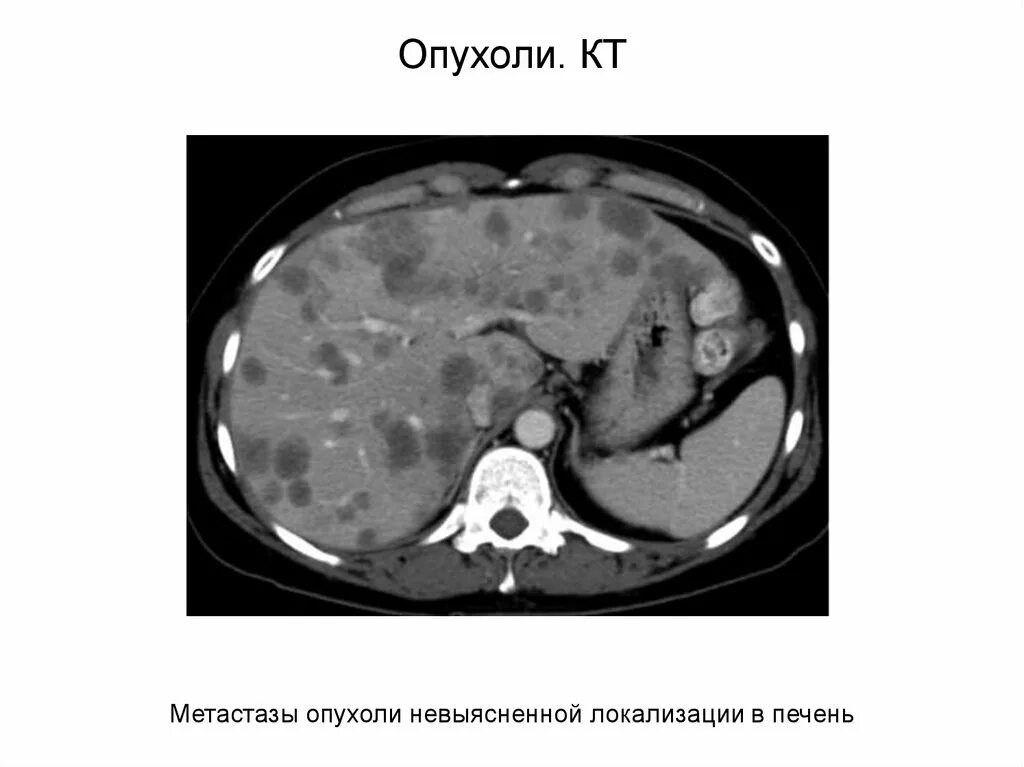

Метастазы рака почки